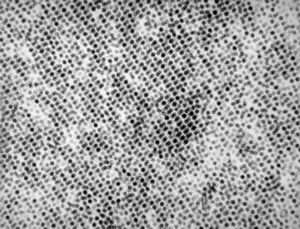

F, 24y. | molluscum contagiosum … virions

F, 24y. | molluscum contagiosum

F, 24y. | molluscum contagiosum

F, 7y. | molluscum contagiosum … virions

F, 7y. | molluscum contagiosum … virions

F, 24y. | molluscum contagiosum … virions